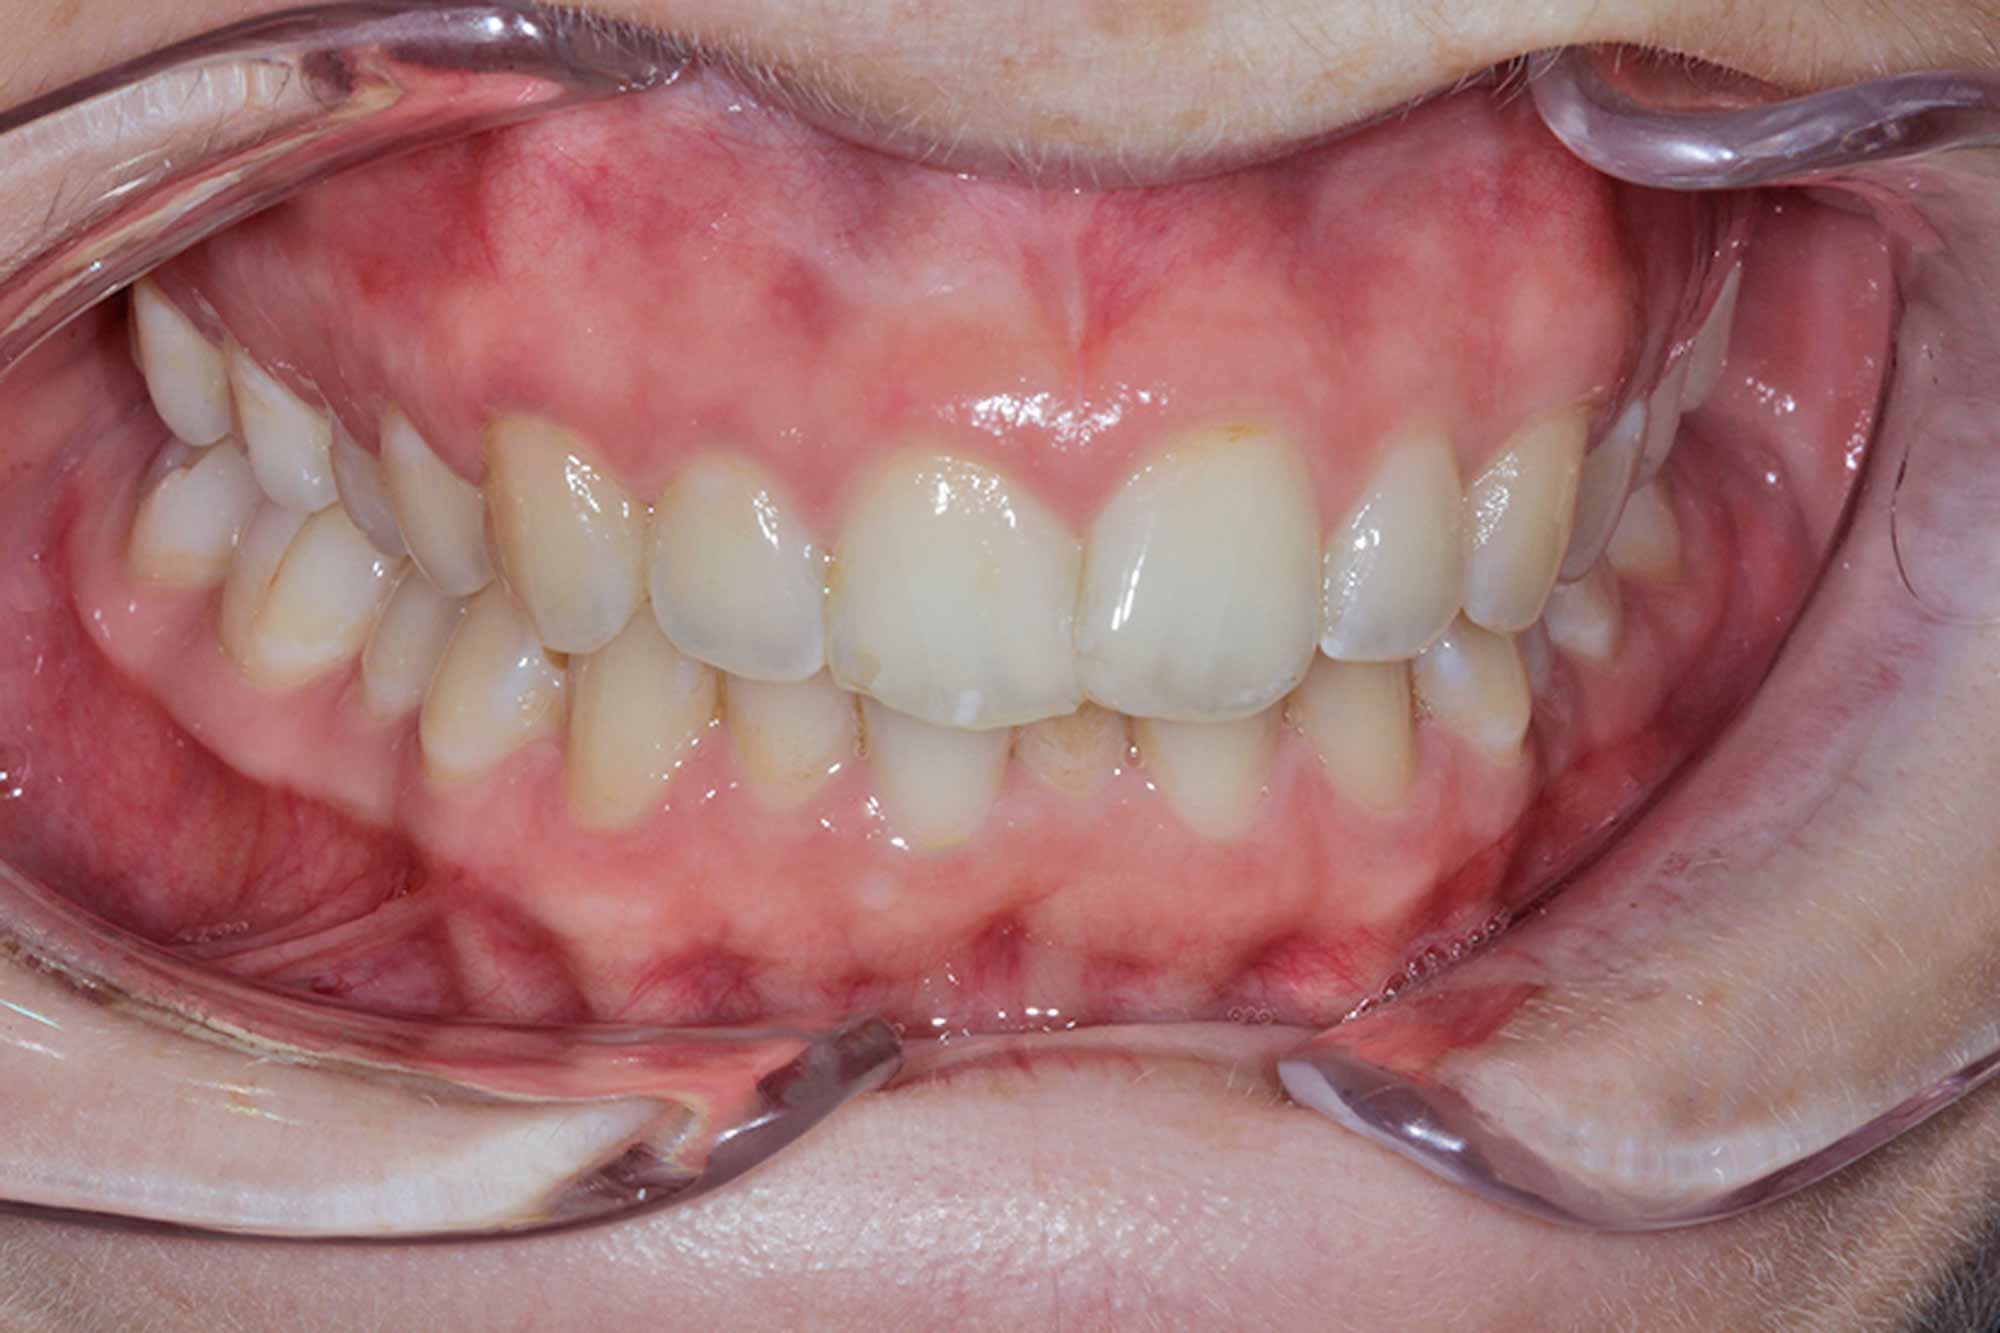

Once we achieved her desired alignment result, the discussion naturally shifted to tooth whitening, and the colour and shade the patient wanted to aim for.

We ultimately achieved a BL1 result, which well exceeded the patient’s expectation.

I achieved this with six weeks of night time whitening, which is fast becoming the norm for those desiring much whiter finishes.